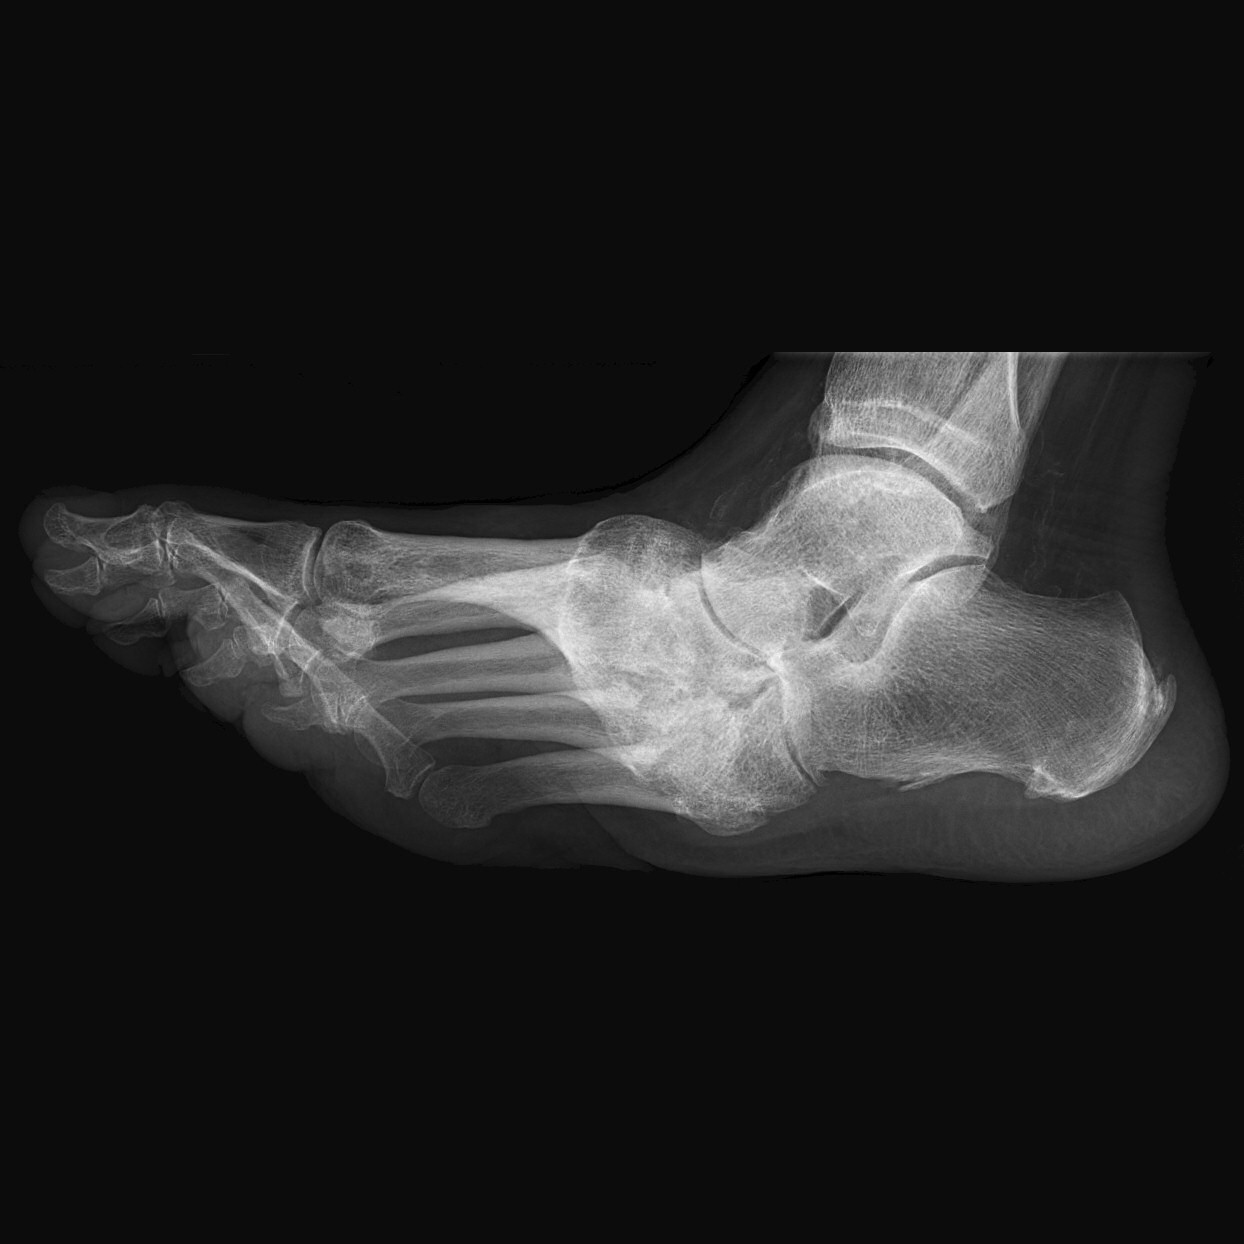

Gammal, läkt charcotfot